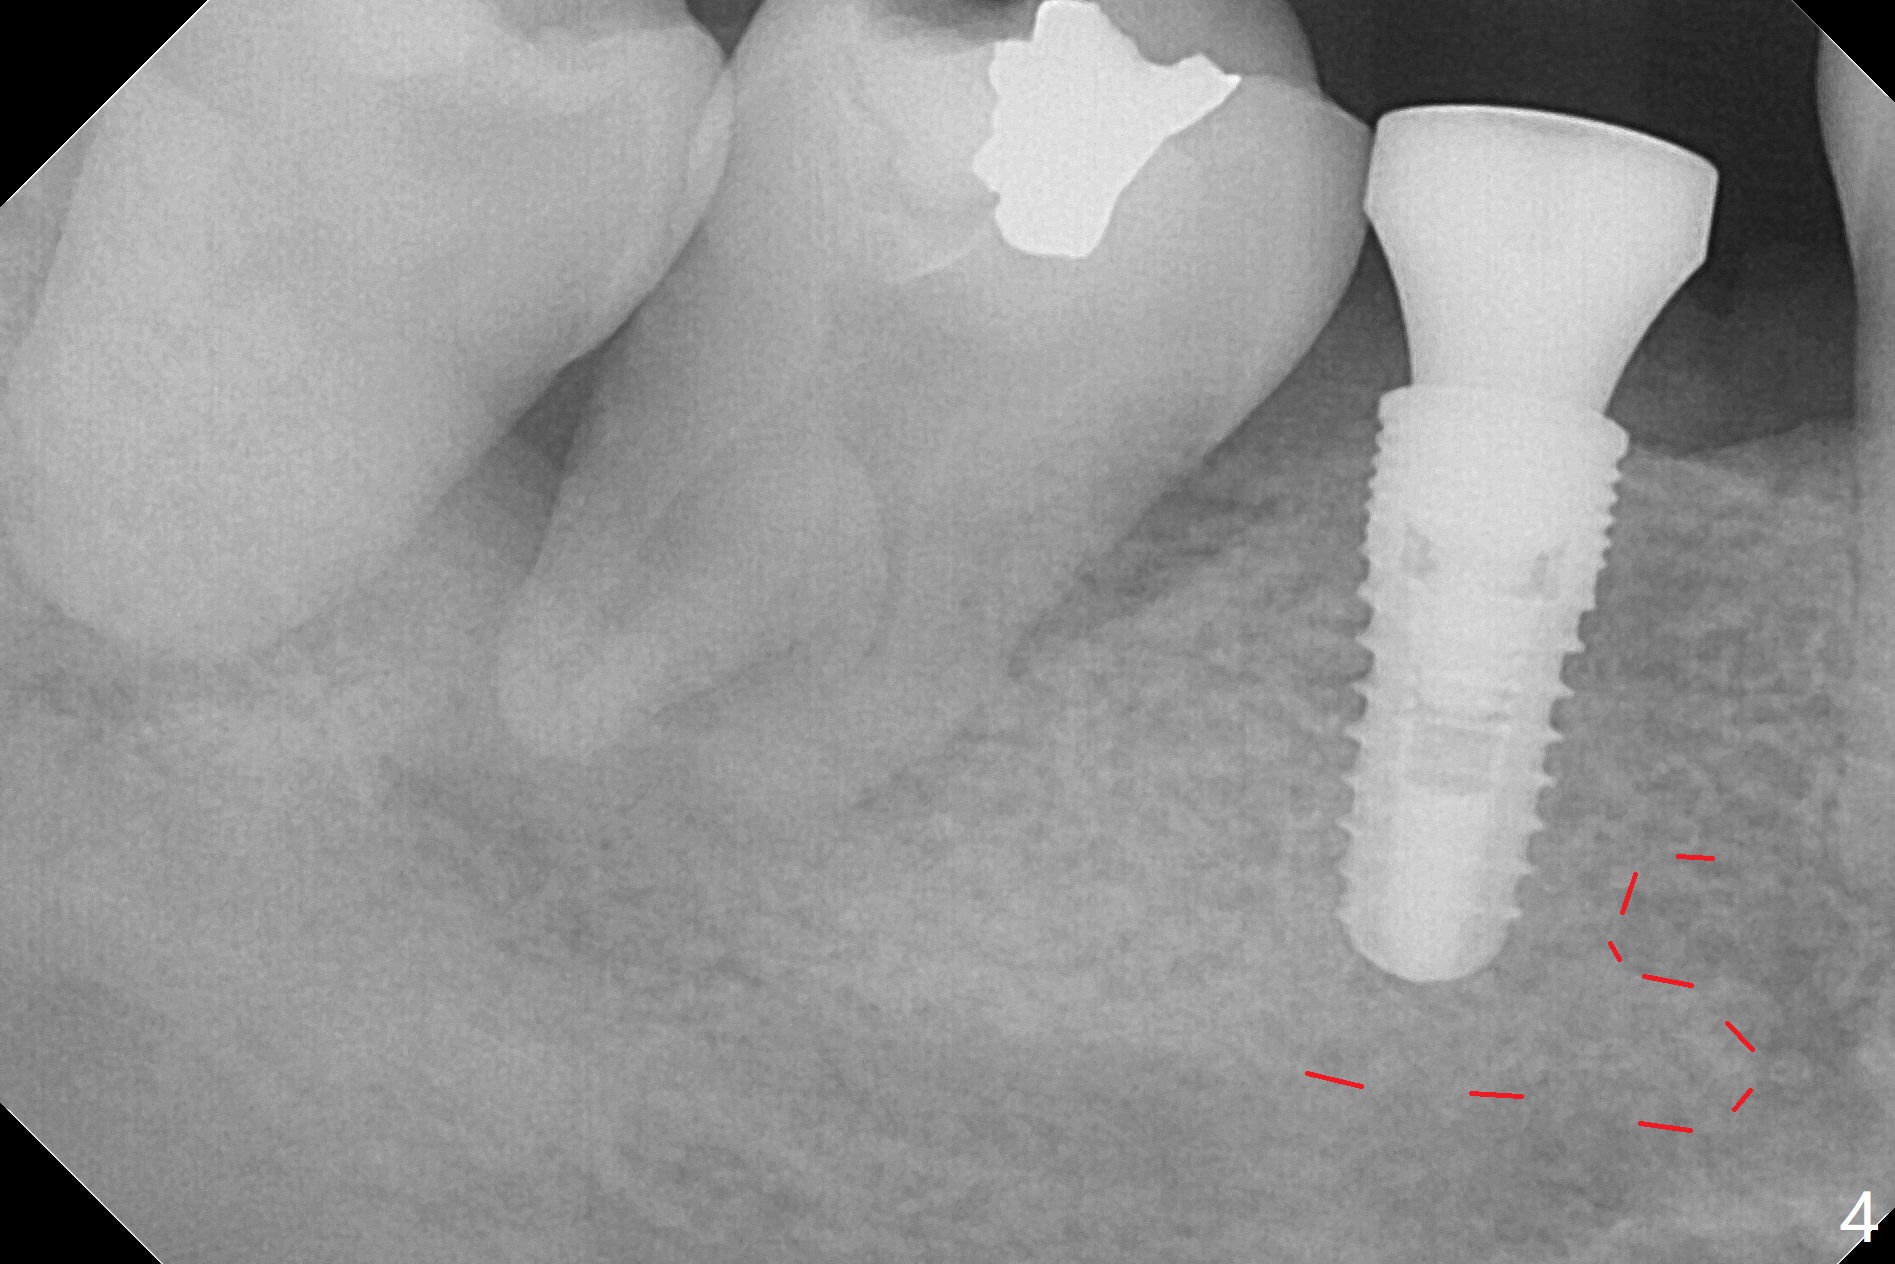

The ridge at #30 is not so narrow (Fig.1). Initial depth is 10 mm with 2 mm from the Inferior Alveolar Canal (Fig.2,3 red dashed line). A 4.5x10 mm implant is placed with > 50 Ncm; a 6.2x5(3) mm healing abutment placed (Fig.4). The implant is stable and seems to be ready for impression 3 months postop (Fig.5). CT taken 5 months post cementation shows that the implant could be placed more lingually (Fig.6 (coronal section; B: buccal)). Periradicular radiolucency at #31 (Fig.7 *) is continuous with the Inferior Alveolar neurovascular bundle (N). After extraction, care should be taken to remove granulation tissue. The tooth #32 will be extracted simultaneously because of severe bone loss.